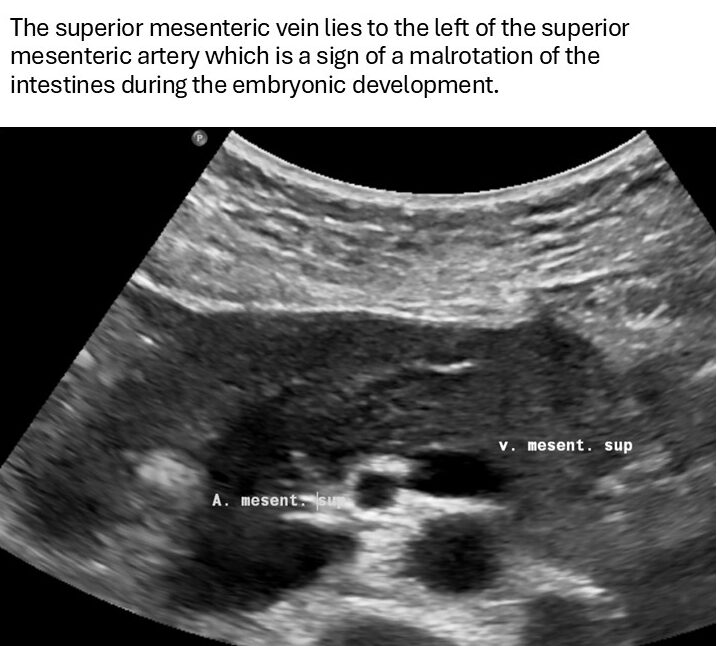

Her symptoms could be explained by the disturbed venous drainage from the small bowel since she had a malformation of her GI tract with a so-called malrotation of the foregut. This implies that the superior mesenteric vein is located left instead of right to the superior mesenteric artery. Thus, the mouth of the superior mesenteric vein into the splenic vein lies far more left compared to patients without this malformation.

- Malrotation of the mesenteric vessels

The patient was born with a malrotation of the foregut. This means that the positioning of the small bowel is not evenly distributed towards the left and right sides of the abdomen. Instead, the small intestines are located mainly on one side of the abdomen. In addition, the positions of the blood vessels of the mesentery were exchanged. Normally, the superior mesenteric vein enters the splenic vein on the right side of the superior mesenteric artery. In this patient, it enters left to the superior mesenteric artery.